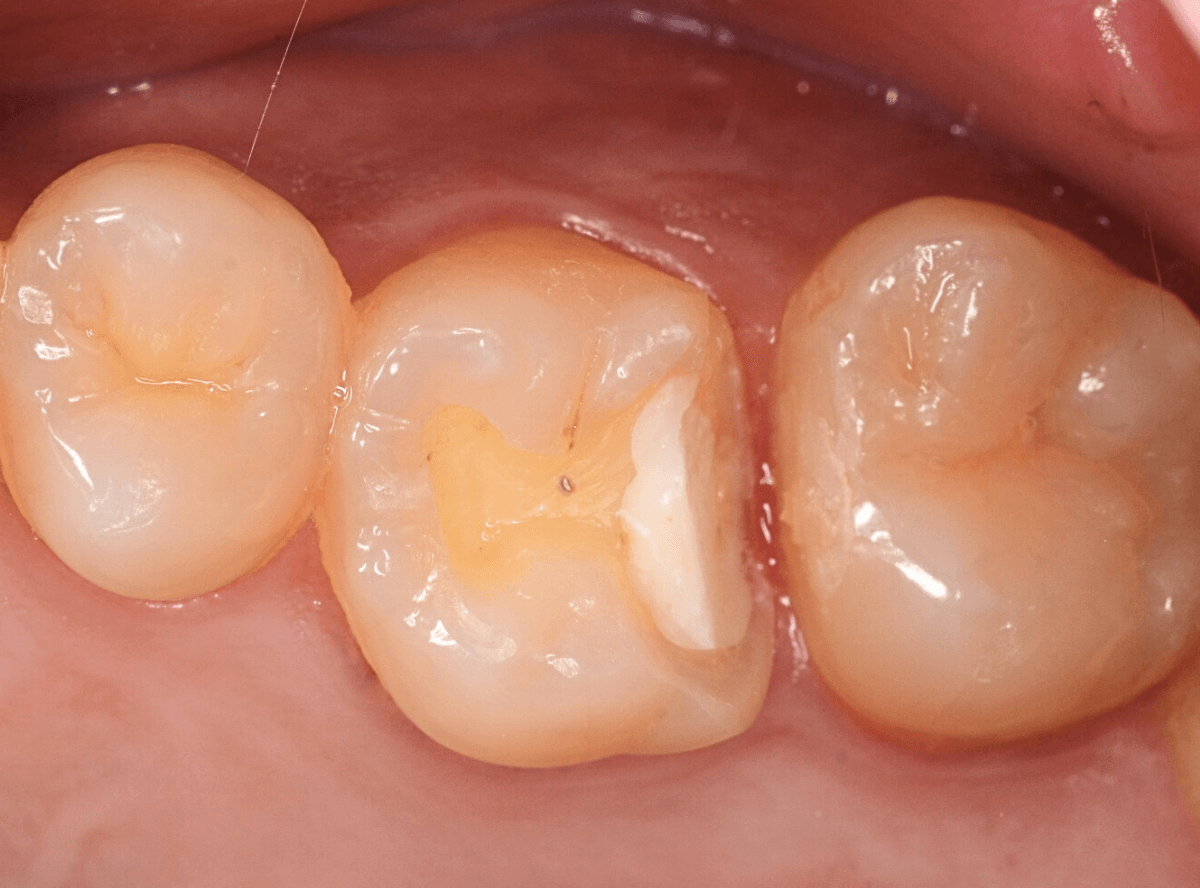

Case.22 痛みはないけど、歯のすきまから大きな虫歯

上の小臼歯の間が虫歯になっていた患者さんです。

症状はありませんし、見た目からも虫歯があるかはわかりませんでした。

レントゲン写真で確認します。

赤い線が虫歯、青い線が歯の神経です。

歯のすきまから両側に虫歯が大きく広がっているのが確認できます。

治療を開始します。

少し削ると、中からすぐに虫歯が出てきました。

ある程度、虫歯を除去したところで、う蝕検知液で確認します。

赤く染まっている部分が虫歯です。

まだまだ虫歯が中で残っている状況で、かなり深い虫歯なのが確認できます。

全ての虫歯を除去しました。

レントゲン写真からある程度確認出来ましたが、歯の神経スレスレまで虫歯が進行していました。

ここまで虫歯が進行していても、全く症状を感じない事も多いです。

そして、ある時急に痛みを感じるのです。

虫歯は急に進行しません。

治療後の定期検診で確実に食い止めましょう。